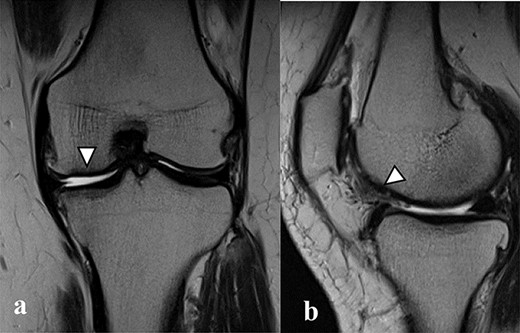

There were cartilage defects (arrowhead) in the medial femoral condyle and trochlea of the left knee (a, b).

Articular cartilage injury was shown in the medial femoral condyle (arrowhead) (2.5 × 3.5 cm; Outerbridge classification, Grade III) and trochlea (arrowhead) (1.3 × 1.7 cm; Outerbridge classification, Grade III) (a, b).

A 42-year-old female (BMI, 27.4 kg/m2) presented with 2 years of left knee medial joint pain. Active range of motion (ROM) in the left knee was from 0 to 140 degrees with no extension lag. Preoperative Tegner scores, Lysholm scores and Knee Injury and Osteoarthritis Outcome (KOOS) scores are shown in Table 1. Preoperative radiographs of the left knee joint showed mild medial osteoarthritis (OA) of the knee and hip–knee–ankle (HKA) angle of 1.5-degree varus. 1.5-Tesla MRI was performed on unit (Toshiba, Kawasaki, Japan) was used with an extremity surface coil. Proton density images were obtained using the fast spin-echo technique. A modified magnetic resonance observation of cartilage repair tissue (MOCART) system was used for the quantitative evaluation of MRI findings of the cartilage injury [15–17]. MRI showed cartilage injury of the medial femoral condyle (MFC) and trochlea of the left knee (Fig. 1).